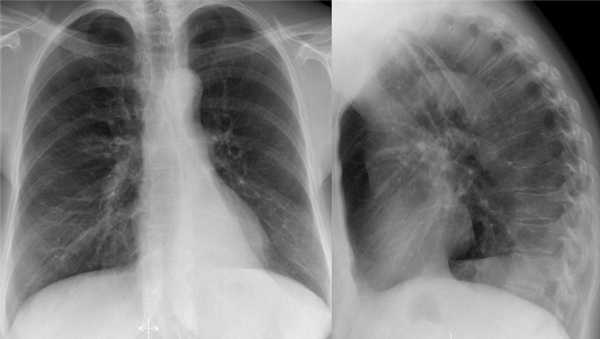

Ателектаз нижней доли правого легкого.

На нижепредставленой рентгенограмме пациента 70 лет, упавшего с лестницы, в плевральной полости определяется скопление жидкости, предположительно являющейся кровью.

Это ателектаз нижней доли правого легкого.

Обратите внимание на правую границу сердца. Правая междолевая артерия не видна потому, как она не окружена воздушной легочной тканью, а закрыта спавшейся нижней долей правого легкого.

Ниже представлены последующие рентгенограммы органов грудной полости того же пациента, на которых ателектаз разрешен.